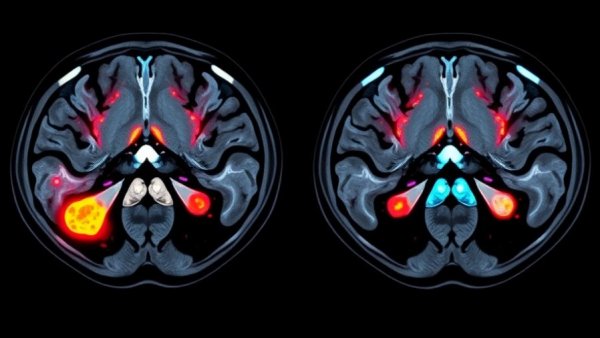

A groundbreaking imaging test has recently emerged that could drastically change how prostate cancer is diagnosed, offering a solution that minimizes invasive biopsies. The PSMA PET/CT scan identifies aggressive prostate cancer cells by making them glow, significantly enhancing detection capabilities while potentially halving the need for traditional biopsy procedures.

Presented at the European Association of Urology Congress, the findings from the PRIMARY2 trial indicated that by incorporating PSMA PET/CT scanning following inconclusive MRI results, medical professionals could significantly reduce unnecessary procedures. Currently, if patients present with suspicious MRI results, they often face biopsies that can be uncomfortable, anxiety-inducing, and carry risks of complications. The PSMA PET/CT scan offers a more targeted approach, allowing only those who truly need a biopsy to undergo the procedure. This not only relieves patient anxiety but also helps in identifying which cancers are risky versus those that are slow-growing and non-life-threatening.